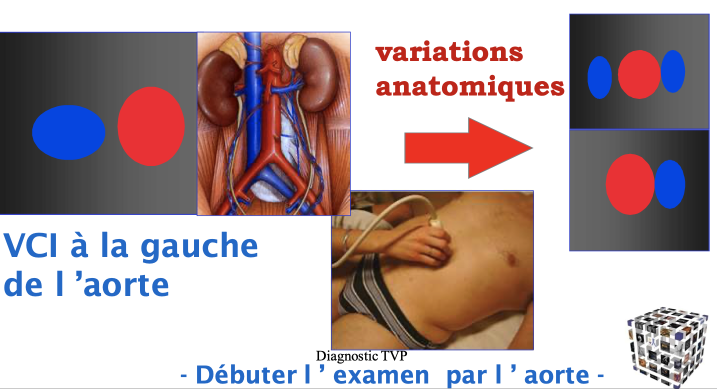

Veine cave Inf

- A faire avec sonde abdominale